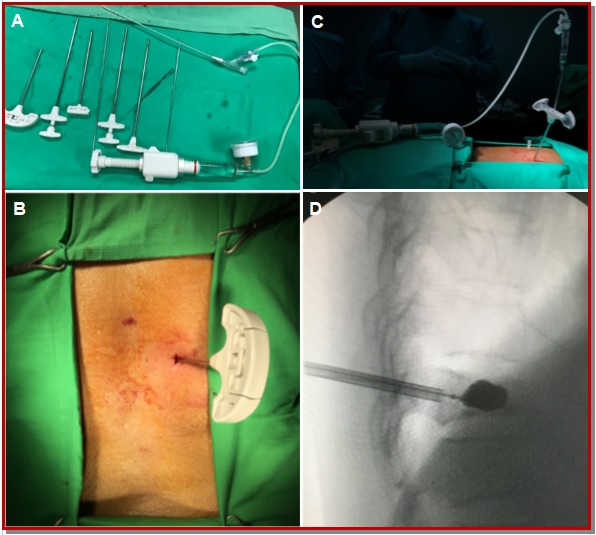

The aim of this study is to evaluate balloon kyphoplasty as a surgical option for osteoporotic thoracolumbar compression fracture. The study was conducted on 30 patients from January 2014 to December 2017. The anterior vertebral height, kyphotic angle and functional evaluation by Oswestry disability index (ODI) and visual analogue scale (VAS) score were recorded preoperatively, immediate post-operatively at 3, 6, 12 months and yearly then on. All patients showed improvement in mean kyphotic angle from 16.4 ± 3.5 to 5.6 ± 1.7 post-operatively and 8.4 ± 1.6 at final follow-up. There was significant increase in mean anterior vertebral height from 51 ± 7.3% before surgery to 75.5 ± 7.4% at one day after surgery and 71.2 ± 3.2% at the last follow-up. There was significant improvement in mean VAS score from 8.1 ± 0.9 before surgery to 2.2 ± 0.4 at one day, and 2.4 ± 0.3 at final follow-up. The improvement in patients’ ODI score after surgery from 71.4 ± 3.4 to 26.0 ± 4.8 at one day and 21.2 ± 5.5 at final follow-up was noted. The mean operating time was 45.5 ± 15.5 min for each vertebra. Within first day of surgery improvement in pain relief and mobility was experienced by all patients. The orthopedic balloon ruptured in one patient and it was replaced then procedure was continued with no complications. There were no neurological complications in all cases and there was no infections and any occurrence of symptomatic pulmonary embolism. In conclusion, balloon kyphoplasty is a good minimally invasive procedure where along with reduction of pain and disability there is also restoration of sagittal alignment post-operatively.